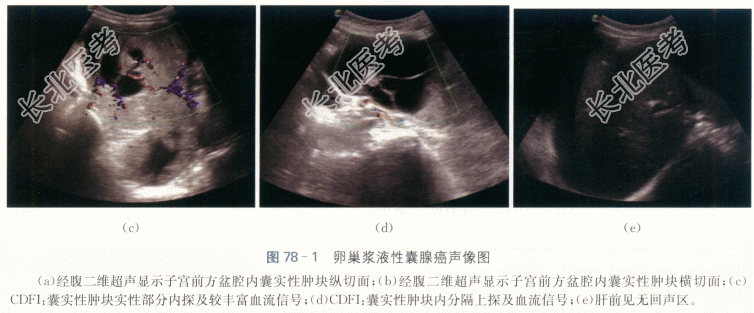

患者,女性,65岁,因“腹胀、左下腹痛伴恶心呕吐3天”就诊。患者自诉入院前3天出现腹胀、左下腹阵发性疼痛,疼痛逐渐加剧,伴恶心呕吐,呕吐后腹痛不缓解。否认头晕、发热、咳嗽咳痰、咯血、肛门坠胀感等不适。入院前一天于当地医院对症支持治疗,腹痛无明显缓解,遂至我院就诊。已绝经15年,绝经后无阴道流血流液等不适,既往月经规律,否认痛经、经量增多等不适。

患者下腹部可扪及巨大包块,上界平脐,张力大,活动度欠佳,有压痛,左侧明显,宫体触诊不清,宫颈光滑,无举痛及接触性出血。

CRP59.86mg/L,CA125100.8IU/ml,血常规、肝肾功能(-)。

- 简答题1、患者的诊断及超声依据是什么?

- 简答题2、请描述浆液性囊腺癌的特征性声像图表现。